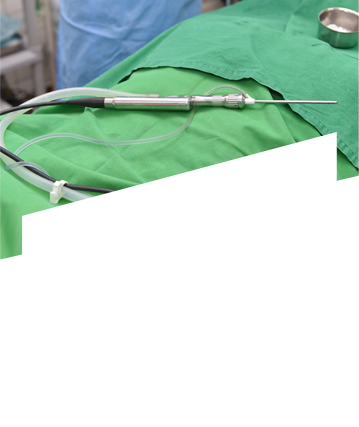

축농증 수술 네비게이션 장비 강남점 도입!

“실시간 교통상황보다 정확한 실시간 콧속상황”

네비게이션 축농증 수술 동영상으로 직접 확인해보세요

• 축농증 내시경 수술

수술 도구 삽입